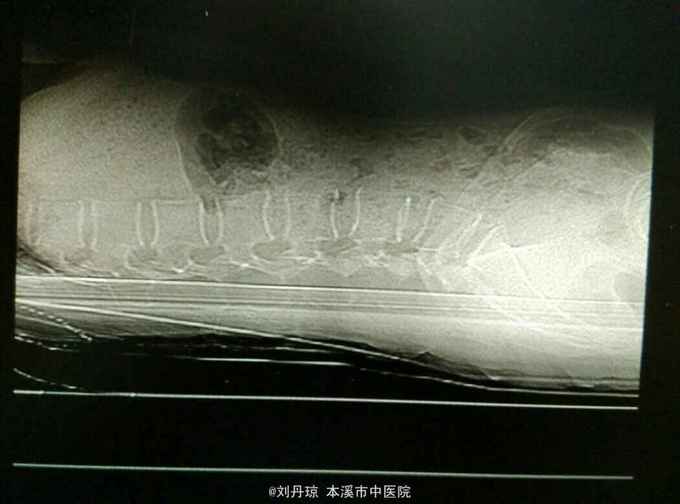

腰痛伴有右下肢放射痛三年,加重十天。患者三年前因抬重物腰部刺痛,休息一周后好转,十天前因开车劳累4.5小时后又洗澡,第2天即感右下肢放射痛难以忍受,遂由门诊收入院治疗。

查体:L5—S1棘突旁压痛阳性。直腿抬高实验。左70度,右30度。加强试验左侧阴性,右侧阳性。腰椎功能障碍。CT:L5—S1椎间盘突出。